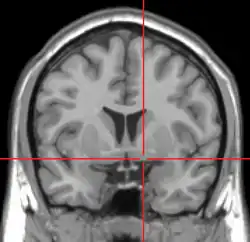

![]() Intermediate magnification micrograph of the nucleus basalis. LFB-HE stain. | |

In the human brain, the nucleus basalis, also known as the nucleus basalis of Meynert or nucleus basalis magnocellularis, is a group of neurons located mainly in the substantia innominata of the basal forebrain.[1] Most neurons of the nucleus basalis are rich in the neurotransmitter acetylcholine, and they have widespread projections to the neocortex and other brain structures.[2]

The nucleus basalis in humans is a somewhat diffuse collection of large cholinergic neurons in the basal forebrain.[2] The main body of the nucleus basalis lies inferior to the anterior commissure and the globus pallidus, and lateral to the anterior hypothalamus in an area known as the substantia innominata.[1] Rostrally, the nucleus basalis is continuous with the cholinergic neurons of the nucleus of the diagonal band of Broca.[1] The nucleus basalis is thought to consist of several subdivisions based on the location of the cells and their projections to other brain regions.[2] Occasional neurons belonging to the nucleus basalis can be found in nearby locations such as the internal laminae of the globus pallidus and the genu of the internal capsule.[1]